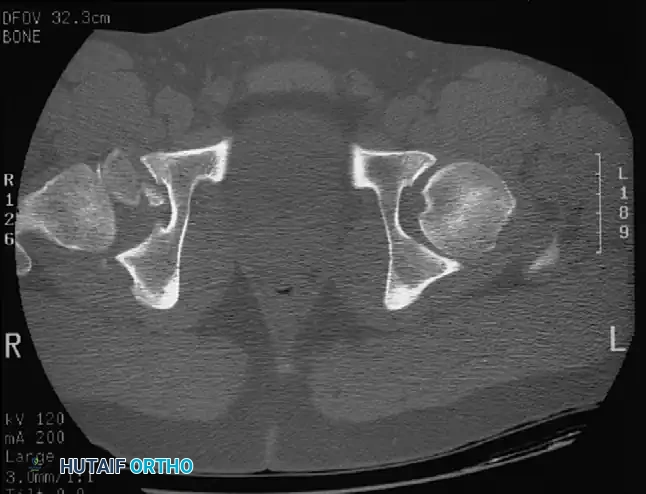

If the reduction is concentric, the patient must undergo a high-resolution CT scan of the pelvis with thin (2-3 mm) axial, coronal, and sagittal reformats. CT is vastly superior to plain radiography for identifying intra-articular fragments, subtle acetabular wall fractures, and femoral head impaction injuries.

Fig. 52-46 Axial CT scan clearly demonstrating a retained osteochondral fragment interposed between the femoral head and the acetabular dome. Operative excision is strictly indicated.

CT scan of the pelvis providing detailed visualization of the posterior wall comminution and the relationship of the femoral head to the acetabular columns.